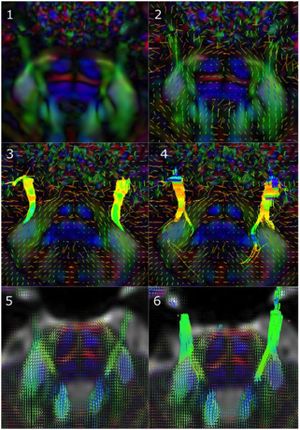

AAV-mediated Direct in vivo CRISPR Screen Identifies Functional Suppressors in Glioblastoma

Publication: Nat Neurosci. 2017 Oct;20(10):1329-41. PMID: 28805815 | PDF Authors: Chow RD, Guzman CD, Wang G, Schmidt F, Youngblood MW, Ye L, Errami Y, Dong MB, Martinez MA, Zhang S, Renauer P, Bilguvar K, Gunel M, Sharp PA, Zhang F, Platt RJ, Chen S. Institution: Department of Genetics, Yale University School of Medicine, New Haven, CT, USA. Abstract: A causative understanding of genetic factors that regulate glioblastoma pathogenesis is of central importance. Here we developed an adeno-associated virus-mediated, autochthonous genetic CRISPR screen in glioblastoma. Stereotaxic delivery of a virus library targeting genes commonly mutated in human cancers into the brains of conditional-Cas9 mice resulted in tumors that recapitulate human glioblastoma. Capture sequencing revealed diverse mutational profiles across tumors. The mutation frequencies in mice correlated with those in two independent patient cohorts. Co-mutation analysis identified co-occurring driver combinations such as B2m-Nf1, Mll3-Nf1 and Zc3h13-Rb1, which were subsequently validated using AAV minipools. Distinct from Nf1-mutant tumors, Rb1-mutant tumors are undifferentiated and aberrantly express homeobox gene clusters. The addition of Zc3h13 or Pten mutations altered the gene expression profiles of Rb1 mutants, rendering them more resistant to temozolomide. Our study provides a functional landscape of gliomagenesis suppressors in vivo. "Raw image stacks were processed using Osirix or 3D Slicer tools. Rendering and quantification were performed using 3D Slicer." Funding:

Autochthonous brain tumorigenesis induced by an AAV-mediated CRISPR library. (a) Schematics of direct in vivo AAV-CRISPR GBM screen design. Top: AAV-mTSG library design, synthesis and production. Bottom: stereotaxic injection of AAV library and subsequent analysis. HPF, hippocampus; LV, lateral ventricle. (b) MRI sections show brain tumors in AAV-mTSG injected mice but not in PBS- or AAV-vector-injected mice. Matching sections are shown. Arrowheads indicate brain tumors. Scale bar, 5 mm. (c) MRI-based volumetric quantification of time-matched tumor size ± s.e.m. Two-tailed Welch’s t test, t17 = 2.62, P = 0.018, mTSG vs. vector or PBS (PBS, n = 2 mice; vector, n = 6; mTSG, n = 18). (d) Kaplan-Meier curves for overall survival (OS) of mice injected with PBS (n = 5), AAV-vector (n = 24) or AAV-mTSG library (n = 56). OS for PBS and vector groups are both 100%; the curves are dashed and slightly offset for visibility; dpi, days postinjection. Log-rank (LR) test, P < 2.20 × 10−16, mTSG vs. vector or PBS. |